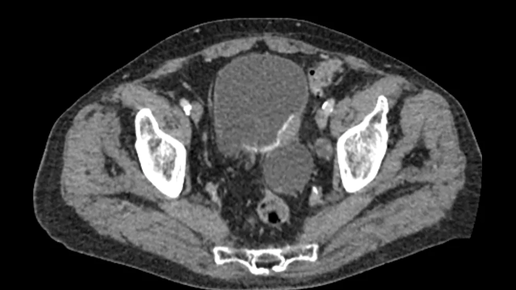

Компьютерная томография (КТ) с контрастом – это диагностическая процедура, при которой внутривенно вводится специальное контрастное вещество для улучшения визуализации определенных органов и тканей на КТ-снимках. Контраст позволяет более четко увидеть структуру и функции различных органов, что делает диагностику более точной и информативной. Основные цели проведения КТ с контрастом: Улучшение визуализации сосудов: Контрастное вещество позволяет четко визуализировать кровеносные сосуды, что необходимо для диагностики аневризм, тромбозов, стенозов (сужений) и других сосудистых заболеваний...